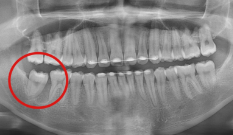

Case 07. 매복된 치아 & 쓰러진 어금니

영구치가 잘못된 방향으로 나거나 제때 올라오지 못하면 턱뼈 속에 갇히는 ‘매복 치아’가 생기며, 교정 치료로 올바른 방향으로 유도·견인해 정상교합 관계를 회복합니다.

어금니가 빠진 뒤 오랫동안 방치하면 인접 치아가 쓰러지고 맞물리던 치아가 내려오는데, 이 경우 쓰러진 어금니를 세우고 위치를 바로잡는 교정 치료로 씹는 힘과 치열의 균형을 되찾을 수 있습니다.

교정 치료 Before & After

• 매복된 치아

Before

After

• 쓰러진 어금니